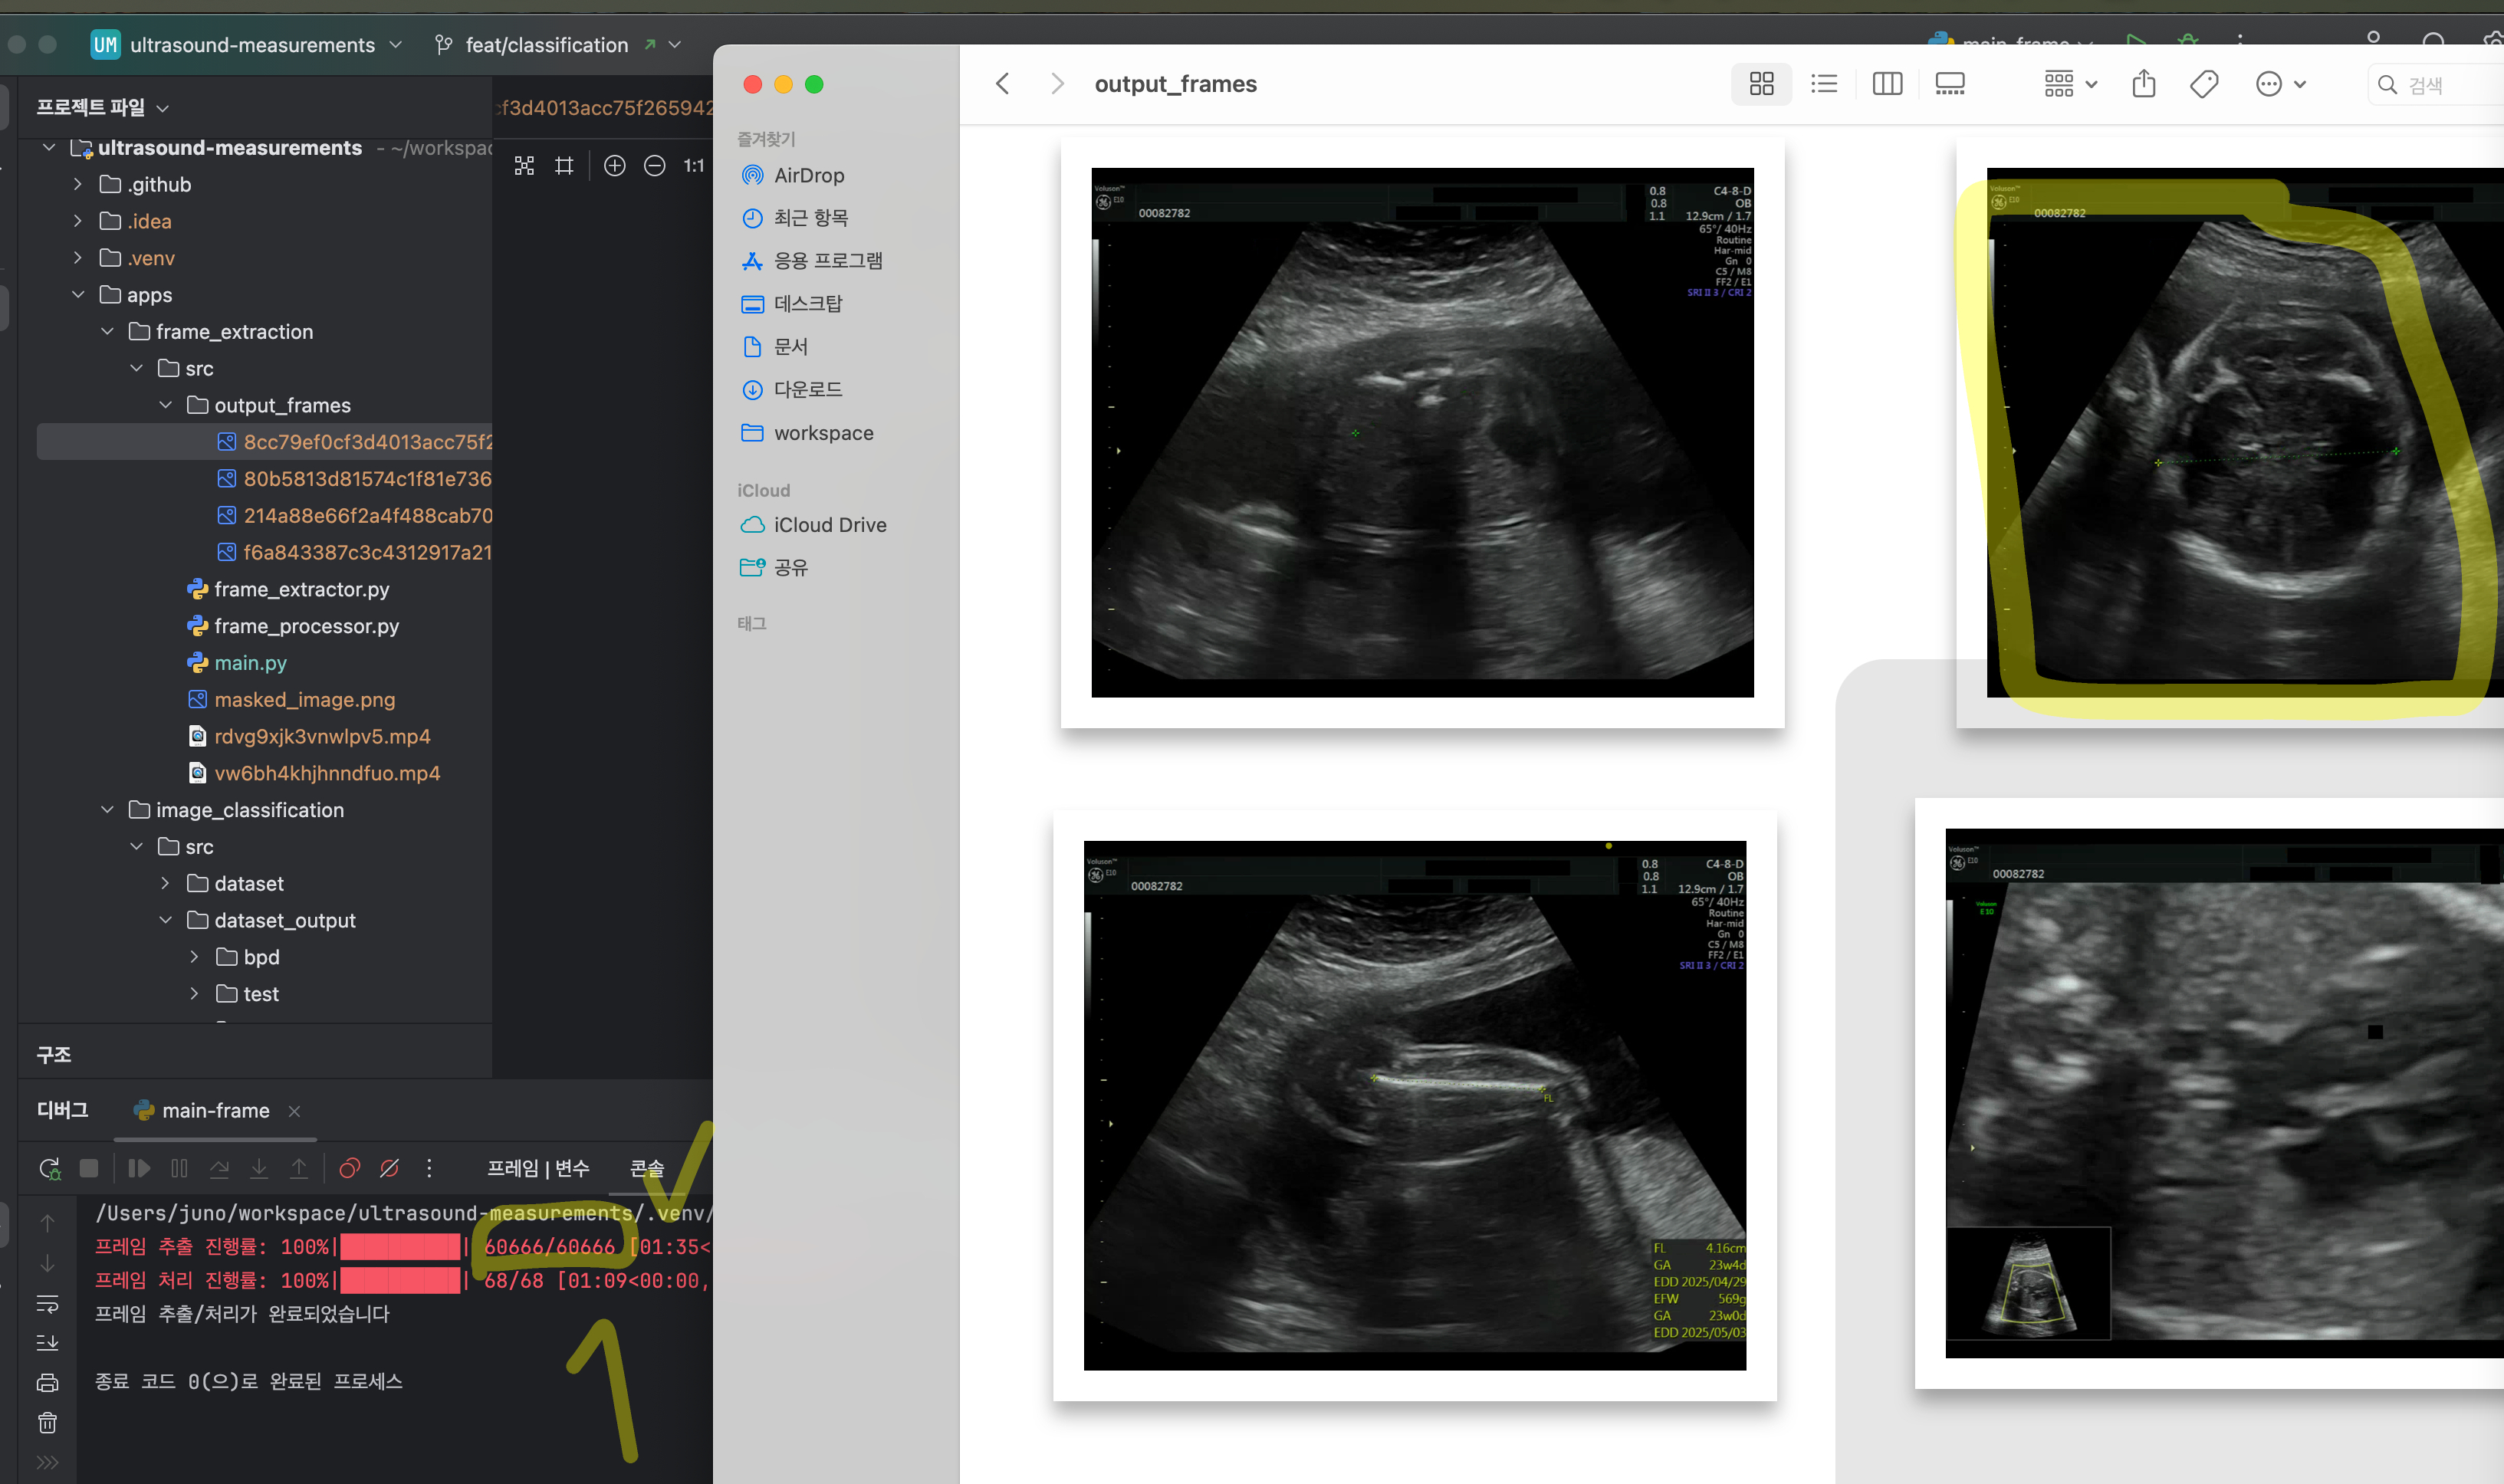

초음파 영상에서 두정골 직경 (Biparietal Diameter, 이하 BPD)을 측정하기 위해 이미지 분석을 진행했다. 하지만 그 이전 단계에서, 먼저 영상을 프레임 단위로 나누는 과정이 필요했다. 영상은 짧게는 3~10분, 길게는 30분 이상까지 존재하는데, 단순히 프레임을 모두 추출하면 30분 영상의 경우 6만 장이 넘는 이미지가 생성된다. 이렇게 많은 이미지에서 BPD 를 측정하기 위해 스케일 바를 탐색하고 ROI(관심 영역)를 찾는 과정은 비효율적일 것 같았다. 그래서 프레임 추출 단계에서 이미지 전처리를 최대한 진행하면 불필요한 데이터를 줄이고 분석 효율을 높일 수 있을 거라고 판단했다.

이를 위해 특정 기준을 설정해 프레임을 선별하는 방식을 시도했다. 예를 들어, 영상 내에서 십자가 모양의 마커가 있는지, 사다리꼴 형태의 초음파 섹터가 포함되어 있는지 등을 조건으로 삼아 유의미한 프레임만 추출하도록 했다. 하지만 실제 구현 과정에서 시행착오가 많았다. 특정 마커가 일정하지 않거나, 초음파 기기마다 영상 구조가 달라 일괄적인 기준을 적용하기 어려웠다. 또한, 조명이나 화질 차이로 인해 예상과 다른 결과가 나오는 경우도 많았다.

이러한 문제를 해결하기 위해 다양한 이미지 처리 기법을 적용하면서 최적의 필터링 방식을 찾아갔다. 여러 시행착오를 거쳐 프레임을 보다 정교하게 추출할 수 있는 방법을 개선했고 이를 해결하기 위한 방법까지 기록을 위해 글을 남긴다.